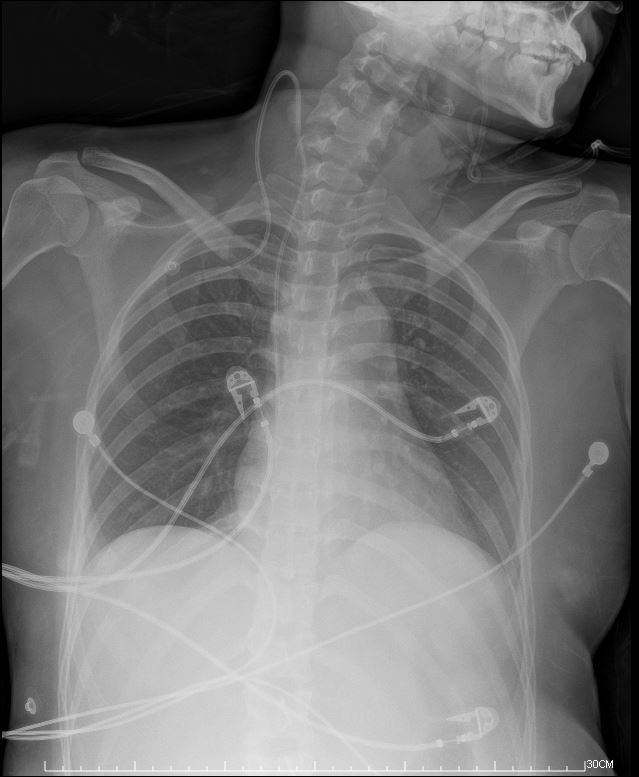

At triage, she wasalert but hypotensive. Labs showed elevated troponin-T and NT-pro BNPlevels and leukocytosis. CXR showed perihilarinfiltrates, and TTE indicated mild LVEF reduction and globalhypokinesia of LV. Given the suspicion of fulminant myocarditis, shebegan IVIG therapy.

**STEP 4: Insert ABIOMED Impella CP® Microaxial Flow Catheter for Cardiogenic Shock** Pre-embedded 2 Abbott Perclose ProGlide™ SMC System sutures at right EIA sheath. Inserted Impella sheath; Advanced 0.18 wire to LV with pigtail, and checked Impella CP device for function and primed with saline. Positioned Impella tip in LV using fluoroscopy; removed guidewire and connected to console. Confirmed Impella function; secured access site.